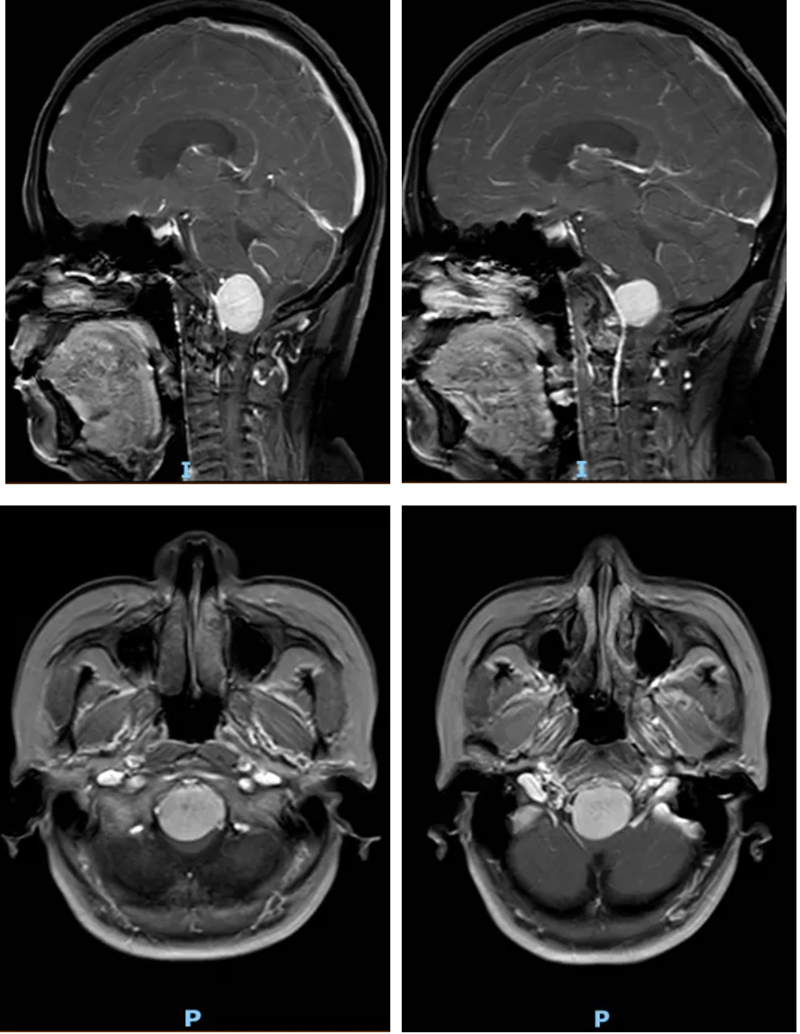

進一步檢查后,金陽醫院神經外科三病區團隊明確了李女士的病情。李女士的腫瘤生長位置極為特殊,位于枕骨大孔區。這一區域是大腦與脊髓連接的關鍵通道,被稱為神經外科手術的“生命禁區”,腫瘤恰好位于延髓前方。而延髓作為控制心跳、呼吸、血壓的“生命中樞”,其周邊解剖結構復雜,緊鄰椎動脈和后組顱神經,手術空間異常狹小,操作難度堪稱神經外科領域的技術高峰。

術后復查頭顱CT和MRI結果顯示,李女士腦部的腫瘤被徹底切除,延髓所受壓迫完全解除。術后恢復期間,在神經外科、麻醉科(手術室)、電生理監測團隊、神經重癥及術后護理團隊的多學科協同照料下,李女士恢復順利。她的頭昏、頭痛癥狀徹底消失,肢體肌力明顯改善,未出現任何新發神經功能障礙,目前已逐步恢復正常生活能力。

陳小忠博士表示,枕骨大孔區腦膜瘤雖然罕見,僅占所有腦膜瘤的1.8%~3.2%,但隨著現代神經外科技術的進步,這一曾經的“手術禁區”已被逐步攻克。早期診斷至關重要,對于持續性頸痛伴神經系統癥狀的患者,應盡早完善影像學檢查,避免病情進展至不可逆階段。隨著神經外科邊界的不斷拓展,更多曾被視為禁忌的病變正逐步被攻克,為患者帶來新生希望。(圖/文 鄒書懷、葉皓)